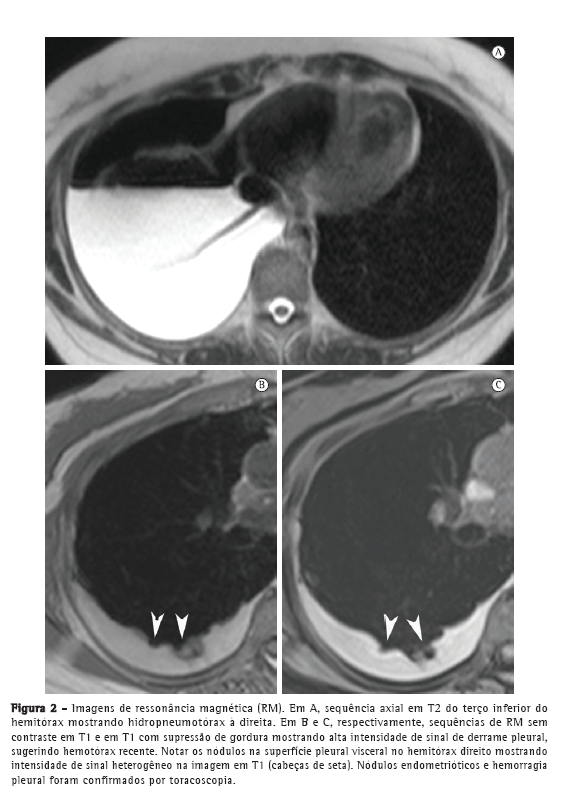

Foi realizada TC, que revelou hidropneumotórax à direita com lesões focais. Na RM de tórax, as sequências T1 e T2 demonstraram hidropneumotórax à direita com pequenas lesões nodulares hiperintensas (Figura 2), sugestivas de endometriomas.

Nos últimos anos, a RM de tórax progrediu muito. Devido a melhorias na velocidade e na qualidade das imagens, a RM está pronta para ser usada na rotina clínica.(7-9) Nos dois casos aqui apresentados, a RM de tórax revelou hidropneumotórax e nódulos arredondados bem definidos na superfície pleural do hemitórax direito. No Caso 1, o derrame pleural apresentou intensidade de sinal intermediária em T1, sugerindo alto conteúdo proteico, provavelmente relacionado a produtos da hemorragia. No Caso 2, o derrame pleural apresentou alta intensidade de sinal, sugerindo hemotórax recente. Os nódulos pleurais observados no Caso 1 mostraram homogeneidade na alta intensidade de sinal em imagens em T1 com supressão de gordura e difusão restrita em imagem ponderada em difusão (IPD). No Caso 2, os nódulos mostraram heterogeneidade na intensidade de sinal nas imagens em T1 e T2, sem restrição de difusão. De forma semelhante à endometriose pélvica,(1,10) os nódulos pleurais da endometriose torácica podem mostrar diferentes intensidades de sinal em imagens em T1 e T2, assim como na variação de restrição de difusão, dependendo da idade da lesão.